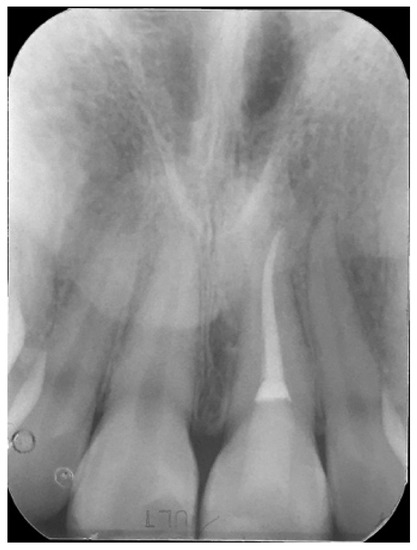

2. Case Presentation